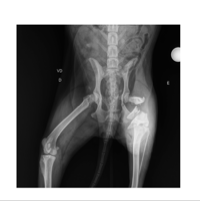

Desde então, estou cuidando dela com todo carinho. Quando a peguei, a Mila estava com bicheira na perna, mas assim que percebi, tratei imediatamente. Com a ajuda de uma veterinária, fizemos o raio-x e descobrimos que ela está com o fêmur quebrado.